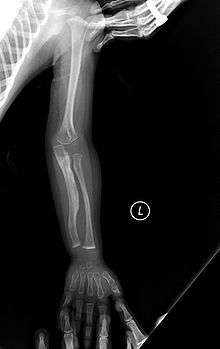

Type V

Having the same clinical features as Type IV, it is distinguished histologically by "mesh-like" bone appearance. Further characterized by the "V triad" consisting of a) radio-opaque band adjacent to growth plates, b) hypertrophic calluses at fracture sites, and c) calcification of the radio-ulnar interosseous membrane.[12]

OI Type V leads to calcification of the membrane between the two forearm bones, making it difficult to turn the wrist. Another symptom is abnormally large amounts of repair tissue (hyperplasic callus) at the site of fractures. Other features of this condition include radial head dislocation, long bone bowing, and mixed hearing loss.

At least some cases of this type are caused by mutations in the IFITM5 gene.[9]